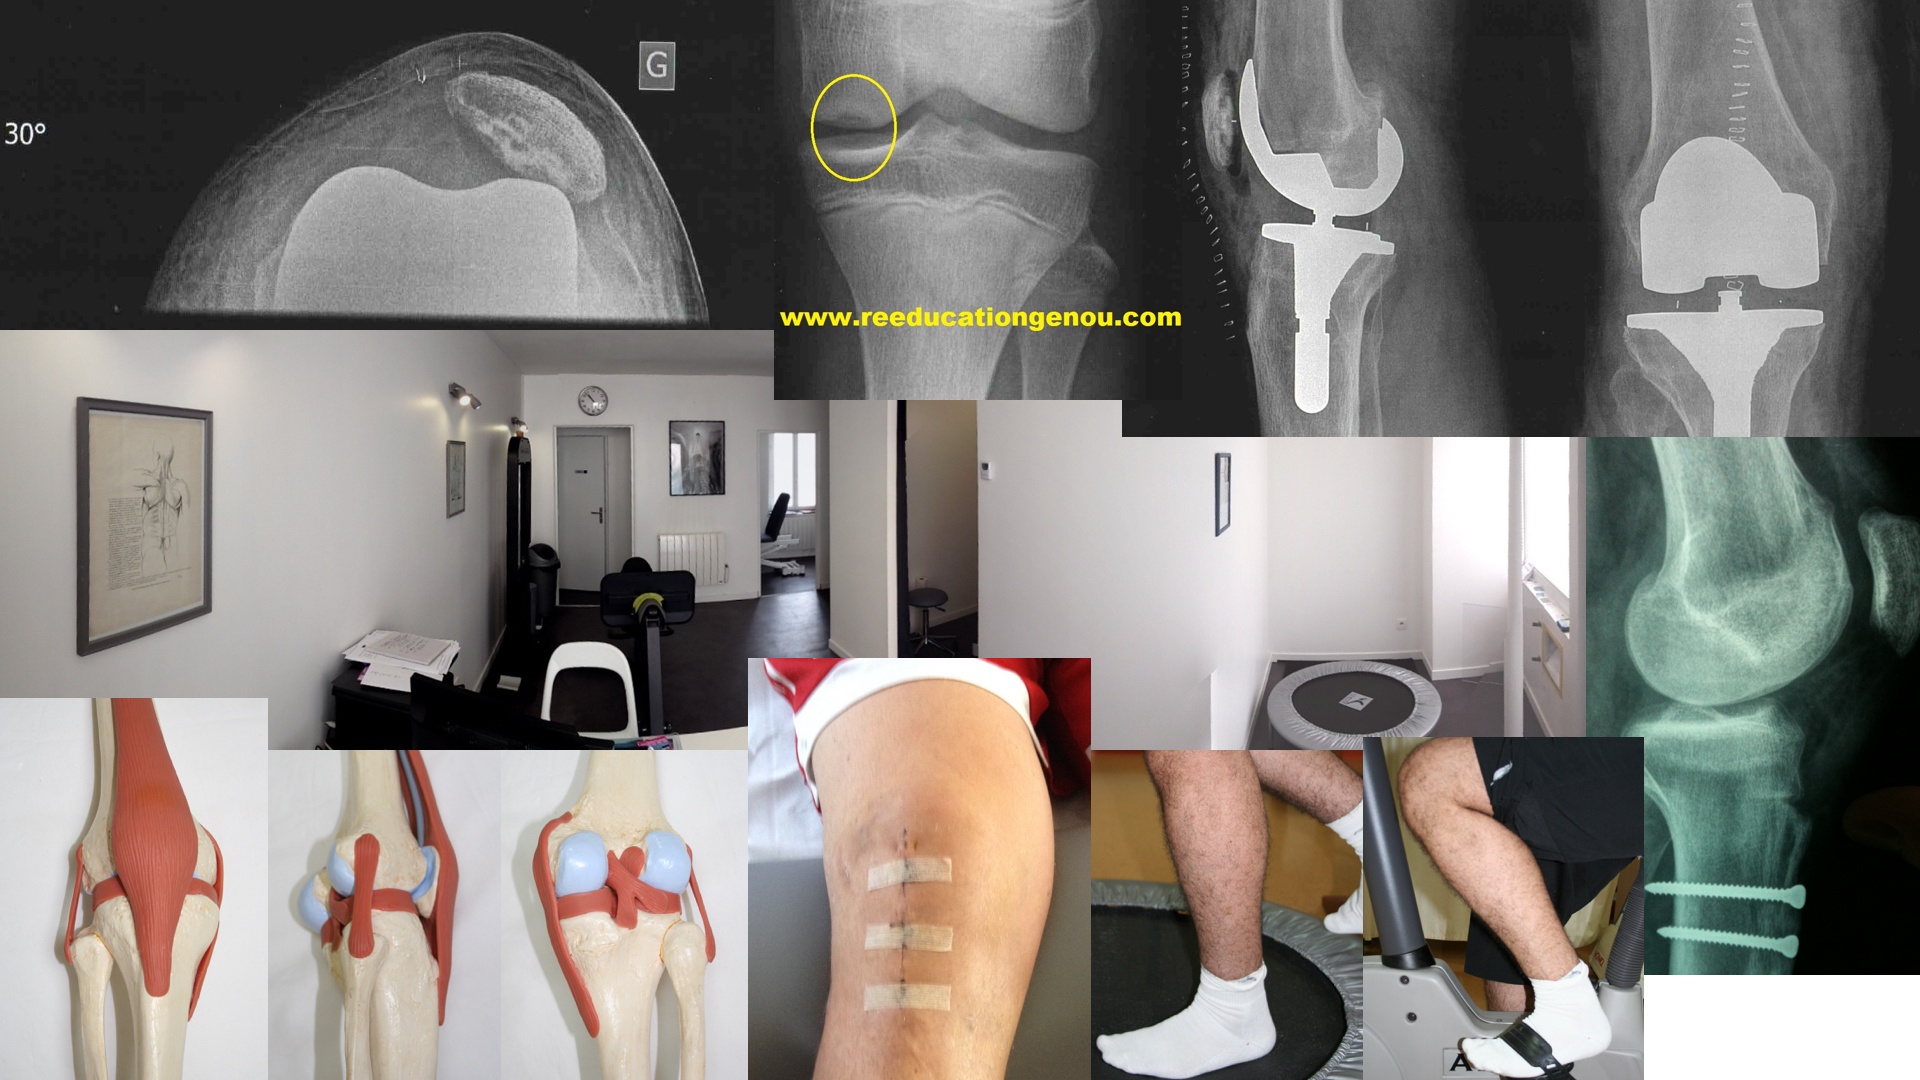

une prothèse articulaire a la même forme que l'articulation originale. Les "compartiments" comme la rotule ou le tibia ou le fémur sont remplacés par des éléments prothétiques en métal chirurgical et polyéthylène .

• On peut ne changer que la partie rotulienne par une prothèse de rotule mais la partie fémorale qui fait face à cette rotule est à changer aussi : c'est la prothèse fémoro-patellaire.

• On peut ne changer que le coté interne ou que le coté externe du genou, c'est la prothèse unicompartimentale (PUC). Le plus souvent c'est le compartiment interne du genou qui est usé alors le chirurgien pose une PUC interne (PUCI).

• Et la totale c'est à dire "rotule + tibia + femur" c'est la prothèse totale de genou (PTG).

1) Prothèse de rotule = fémoro patellaire

• pour les rotules arthrosiques, c'est l'idéal : on ne change que l'arrière de la rotule par une partie en polyéthylène et la partie fémorale doit aussi être prothétique : c'est le principe de la prothèse fémoro patellaire.

Dans les cas où seulement un compartiment en général l'interne du genou est touché, (le coté de la radiographie qui est "pincé") la partie haute, fémorale est remplacée par du métal qui a la même anatomie que l'os initial, la partie basse, tibiale, est remplacée par du polyéthylène.